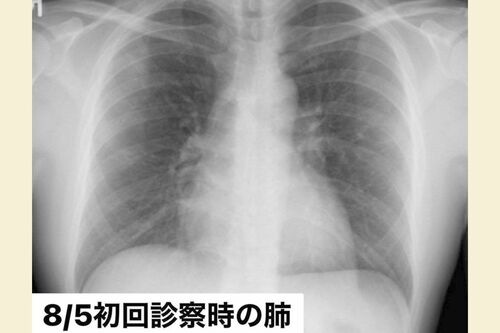

「宿泊療養施設のホテルに着いてすぐ、パルスオキシメータ(血中酸素飽和度を測る機械)で酸素量を測りました。そのとき、『72』という恐ろしい数値が出て。ホテル療養では危険ということで、急遽入院先の病院を探すことになりました。たまたまとある病院のベッドに一つ空きが出たということで、入れたのですが……。もし空きベッドがなく、宿泊療養所に戻っていたとしたら、完全にアウトでした」

約96~99%が正常値で、93%以下になると酸素投与が必要となる。90%を下回ると「呼吸不全」と呼ばれ、その状態が継続すると心臓や脳などに障害を起こすことがある。瀬川さんの数値「72%」は、その「90%」をはるかに下回る、きわめて危険な状況だった。

「でも実際、不思議なことに72%を示していても息苦しさをあまり感じなかったんです。だから、そんな深刻な状況とは思いませんでした。後から医師に聞いたのですが、このときの僕はコロナ患者によくみられる『ハッピー・ハイポキシア(Happy Hypoxia)』=『幸せな低酸素症』だったようです」

ハッピー・ハイポキシアとは、コロナ患者の肺炎が進み、酸素の状態が悪化しても「息苦しさを感じない」状態をいう。自分で気づかないうちに重症化する場合も多く、多くの医師も警鐘を鳴らしている症状だった。